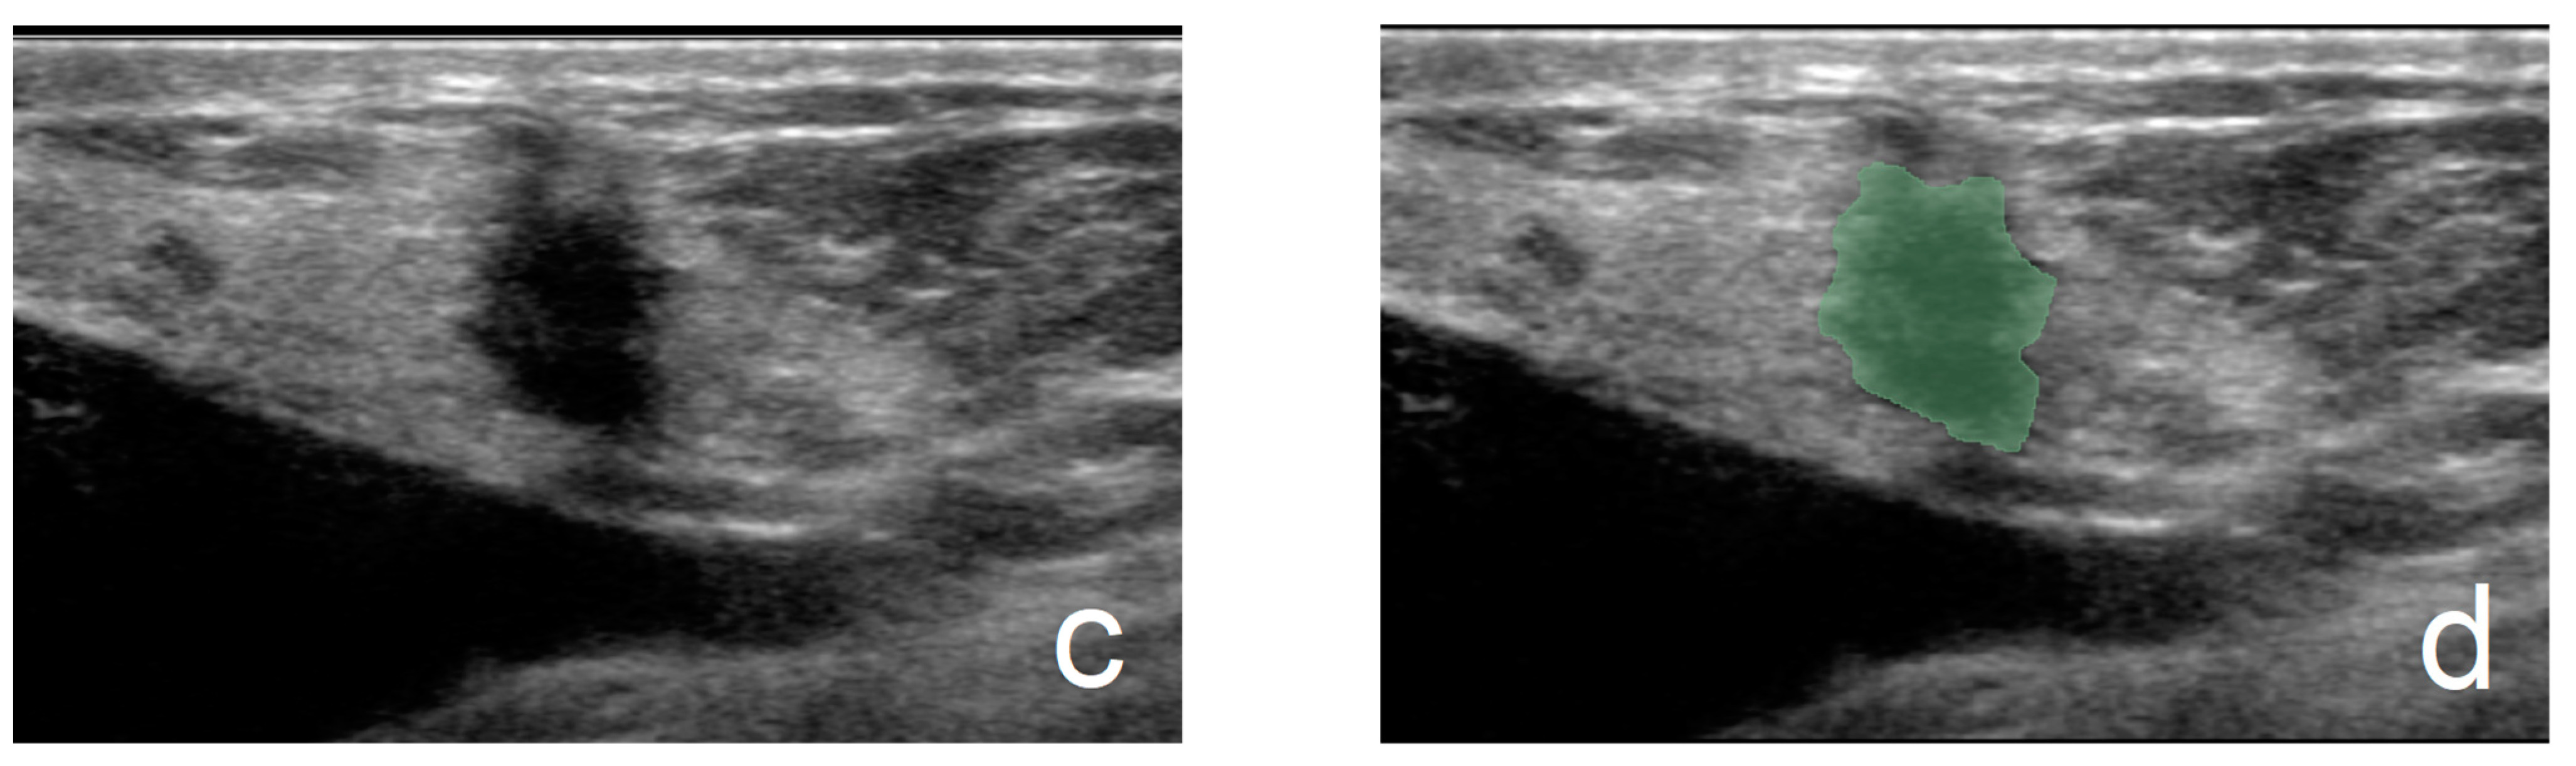

2.4. Acquisition of Ultrasound Pictures, Preprocessing, and ROI Delineation